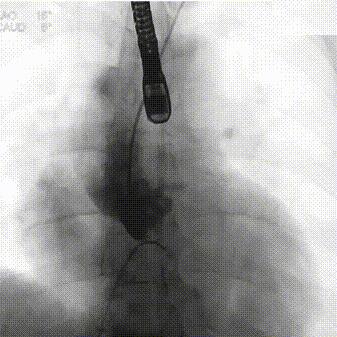

手术影像记录

瓣膜稳定释放至工作位

TaurusOne AV23mm瓣膜瓣下3-4mm 工作位造影

瓣膜完全释放

瓣膜位置理想

瓣膜植入前压差:121mmHg

瓣膜植入后即刻压差:16mmHg